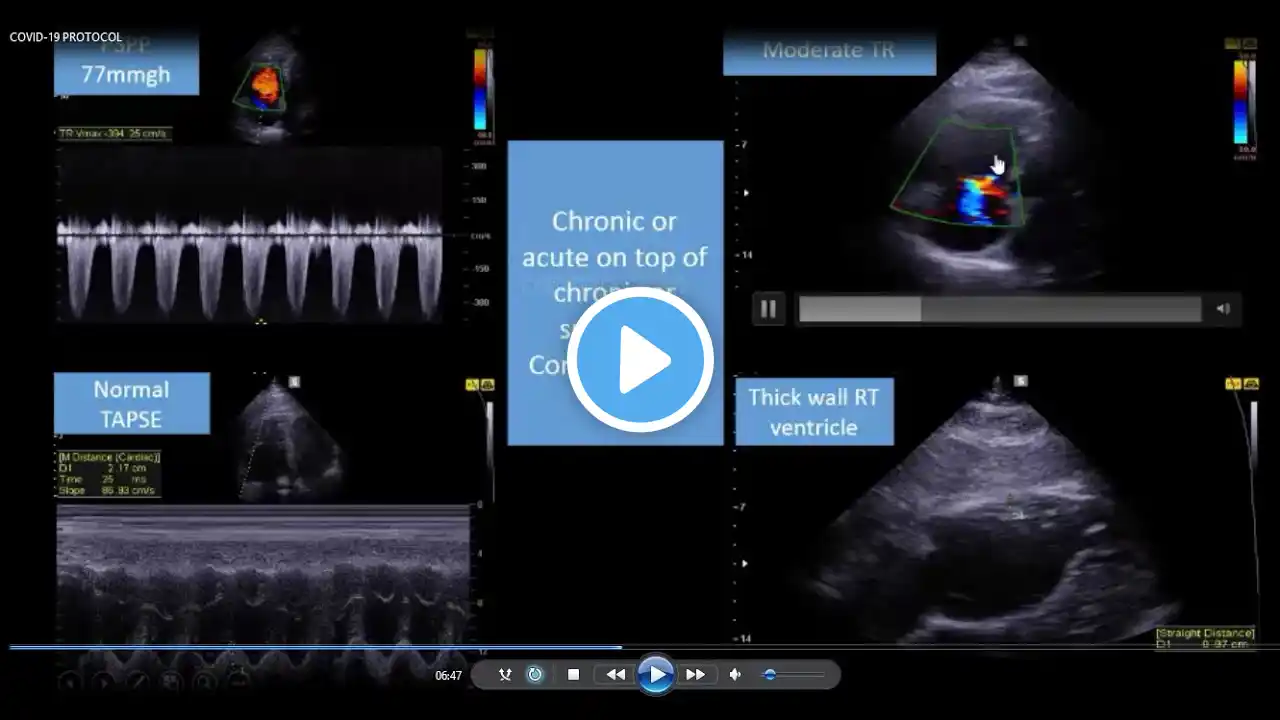

A step by step approach to diagnose all causes of RT ventricle dilatation in COVID-19 by POCUS